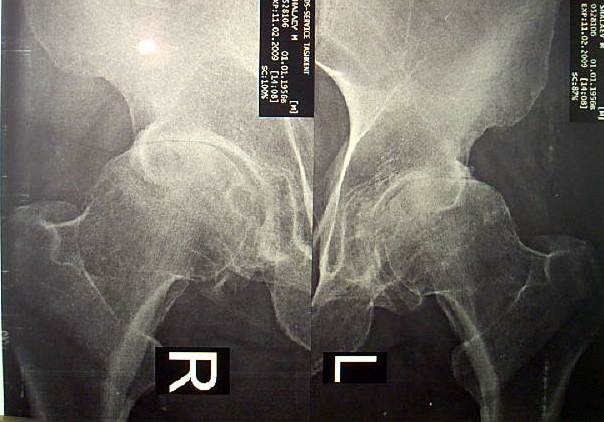

Больному 52 года, среднего роста, весит 110 кг. Около 12 лет болеет подагрой. Движения в т/б суставах ограничены и болезненны. В течении 2 лет периодически получает дипроспан  по 1.0 в каждый сустава (каждые 1.5-2 месяца). От эндопротезирования категорически отказывается, просит восстановить его сустав другими методами.

Имя     : CAM_1531.JPG

Тип     : image/jpeg

Размер  : 32800 байтов

Url     : http://weborto.net:8080/pipermail/ortho/attachments/20090215/da131844/attachment-0002.jpeg